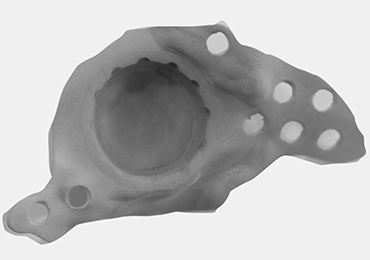

Step 3: The implant model is printed.

Step 4: Depending on the preference of the surgeon, it can be used with or without bone cement.

FINAL PRODUCT: CUSTOM MADE ACETEBULAR REVISION IMPLANT